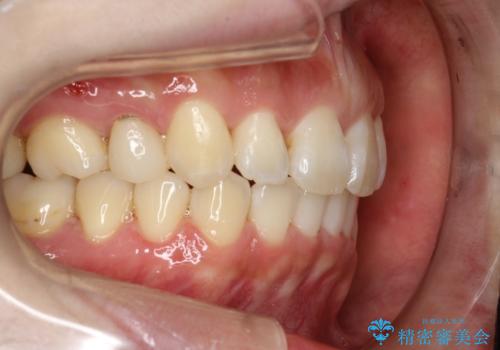

抜歯をして前歯を下げ、ガタつきを取り除く ワイヤー矯正

- 30代女性

- 上顎両側第1小臼歯、下顎左側第2小臼歯の3本を抜歯、ラビアルのワイヤー矯正を計画した。

抜歯矯正は抜歯にできたスペースをつかい、前歯を積極的に下げたり、大きなガタつきを取り除くことができますが、その分時間がかかります。